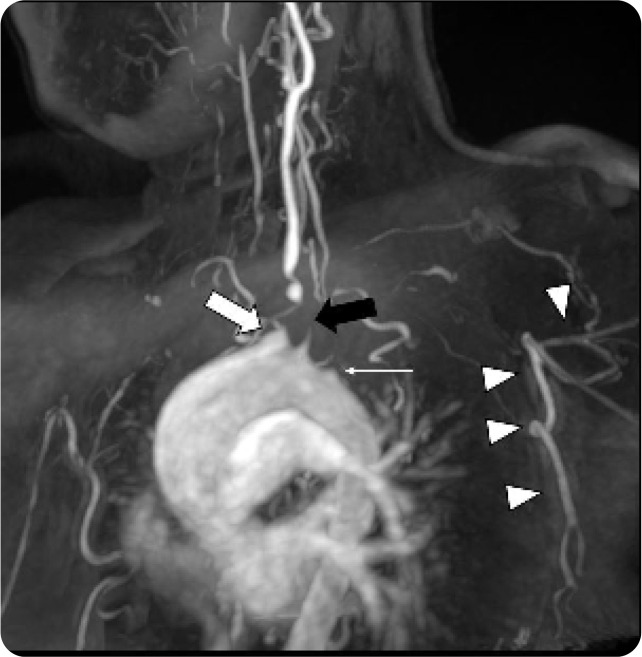

Abstract Image